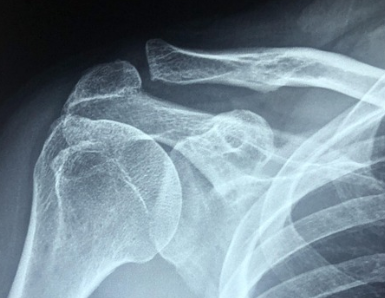

진단에 활용되는 일반적인 방법

회전근개 파열은 다양한 방법으로 진단이 이루어져요. 가장 먼저 하는 건 증상에 대한 문진과 어깨 움직임 확인이에요. 팔을 올리거나 돌릴 때 통증이 특정 방향에서 유발되면 회전근개 문제를 의심할 수 있어요.

도수검사라고 해서, 전문가가 손으로 팔을 움직여보며 반응을 확인하는 방법도 있어요. 예를 들어 '드롭암 테스트'나 '호킨스 테스트' 같은 방식으로 힘줄의 기능을 확인해요.

좀 더 정확한 진단을 위해 초음파나 MRI를 촬영할 수도 있어요. 초음파는 실시간으로 관찰할 수 있고, MRI는 힘줄의 상태를 정밀하게 확인할 수 있기 때문에 정확도가 높아요.

특히 MRI는 파열의 정도와 크기를 파악하고, 수술이나 관리 여부를 결정하는 데 중요한 정보가 되죠. 비용이 조금 들 수는 있지만, 증상이 오래되었다면 한번쯤 검사를 고려해볼만 해요.